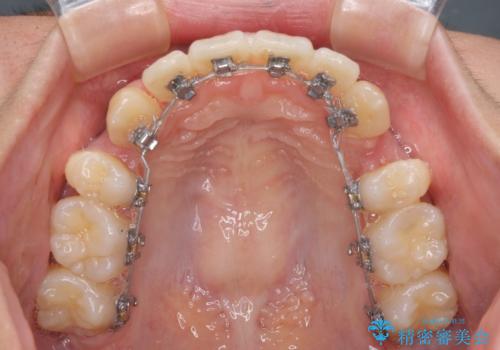

- ハーフリンガル

目立たない装置を希望されたので、上顎が裏側装置のハーフリンガルを選択し、上下左右の小臼歯(計4歯)を抜歯して矯正治療を行うこととしました。

表側のワイヤー矯正に比べると治療期間は長く、費用も高額となりますが、どうしても目立たせたくないという方にはお勧めの抜歯矯正です。